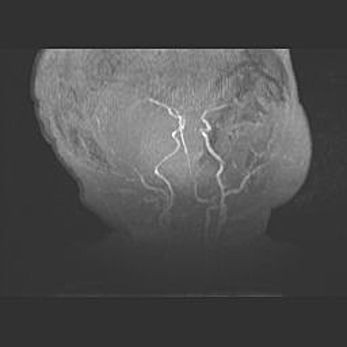

Церебральная ишемия II.

Возраст: 5 дней

Вес: 3400 г

Пол: женский

Окружность головы: 35 см

Срок гестации: 39 недель

Церебральная ишемия – это заболевание, характеризующееся недостаточностью (гипоксией) либо полным прекращением (аноксией) снабжения мозга кислородом по причине закупорки одного или нескольких сосудов. Это приводит к  что метаболическим расстройствам различной степени тяжести в тканях головного мозга, развитию коагуляционных некрозов и гибели нейронов.